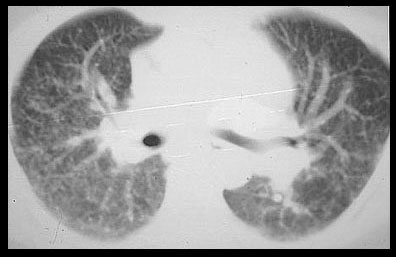

The small ( 2-10mm ) nodules are characteristic of sarcoidosis. These nodules are primarily distributed in the lung tissue along lymphatics. Many are located along the bronchovascular bundles, in the subpleural interstitial space beneath the viseral pleura, and in the interlobular septae. These nodules are much easier to see on computed tomography studies than on radiographs. Computed tomography done with thin ( 1-2mm ) sections and the highest spatial resolution possible is known as high resolution CT (HRCT). HRCT is the best way to show details of lung tissue disease, except for small nodules. On 1-2mm sections, blood vessels in cross section are difficult to differentiate from lung nodules.

Small 5mm nodules are usually shown by CT in patients with sarcoidosis. Many nodules are subpleural, along fissures, and as in this patient, along bronchovascular bundles. The nodules give the vessels (arrow) and fissures a beaded appearance. |